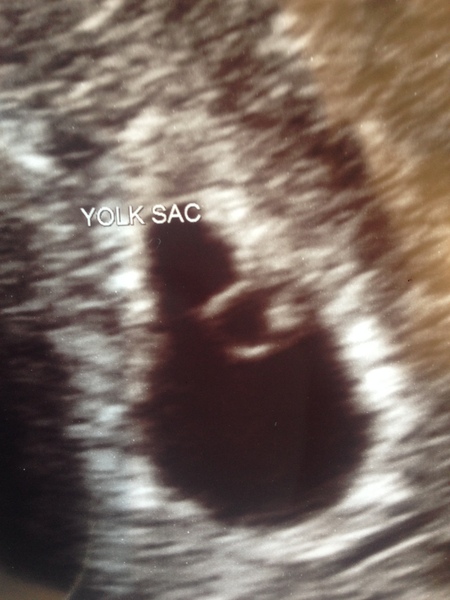

Morning added myself in. Well we managed to get private scan last night and all is good. Have had the best sleep ever!! Saw a tiny heartbeat. If anyone is anxious from previous loss I would recommend it. The bubble is the sac and the tiny white thing is baby yukkaxxxx

@Yukka that is amazing!! I'm loving seeing people's scans - never actually seen one irl so this is incredible. So so happy for you xx

Also @Yukka, that picture it amazing! There's a little bean in there! I'm glad to hear things are going well :)

That’s brilliant news @Yukka. How amazing to hear a heartbeat, you must be so happy. I am definitely going to try and book a private scan now think it will definitely put my mind at ease x

Omg @Yukka that's amazing!!! How many weeks? I've got one next week and I'm so nervous about it!!